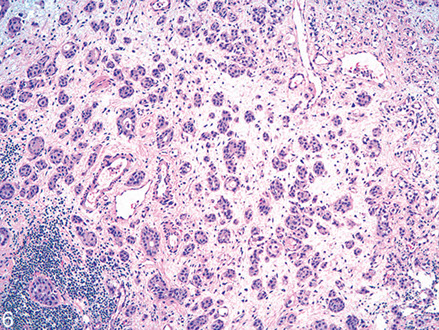

Non Invasive Papillary Carcinoma, High Grade

• Overall disorderly arrangement with irregularly

clustered cells, fused papillae

• Marked atypia analogous to CIS

• Numerous mitotic figures including atypical forms at

all levels

• Dyscohesive single cells

• Prominent nucleoli